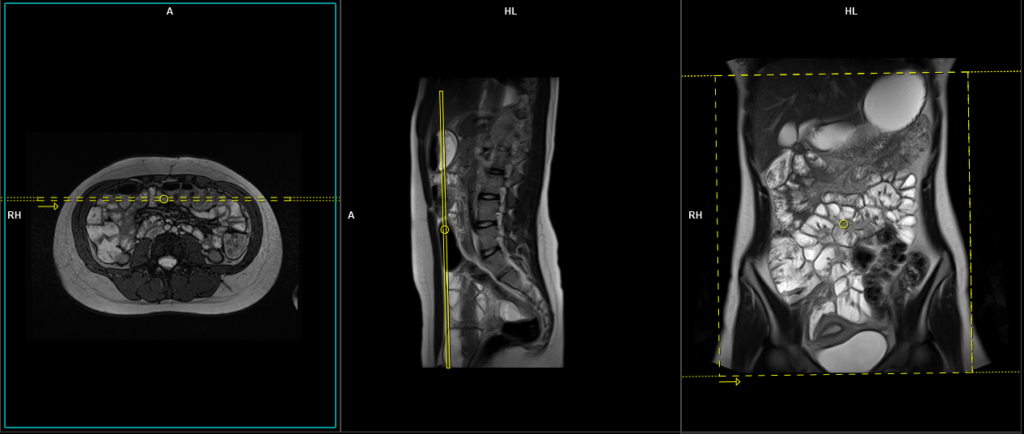

T1 VIBE DIXON \ T1 flash fat sat 3d 1-1.5 mm axial post contrast

Plan the axial slices on the coronal image, position the block horizontally across the abdomen as shown, and ensure that the positioning block is also checked in the other two planes. Establish an appropriate angle horizontally across the abdomen in the sagittal plane. The slices must be sufficient to cover the entire abdomen and pelvis from the stomach to the pubic symphysis. To prevent wrap-around artifacts, phase oversampling, and in the case of 3D blocks, slice oversampling must be used. Instruct the patient to hold their breath during image acquisition. (In our department, we instruct the patients to breathe in and out twice before giving the “breathe in and hold” instruction.)

The axial scan is performed as two separate blocks with a 10-25% slice overlap between them. The scan is performed this way to avoid any RF inhomogeneity-related artifacts by conducting the scans at the isocenter of the magnet. Use the composing function in the scanner to stitch the two blocks together.

Protocol Parameters T1 FLASH Axial

TR 3-4 | TE 1-2 | FLIP 12 | NEX 1 | SLICE 2 MM | MATRIX 320X320 | FOV 350-420 | PHASE A>P | OVERSAMPLE 30% | IPAT ON |